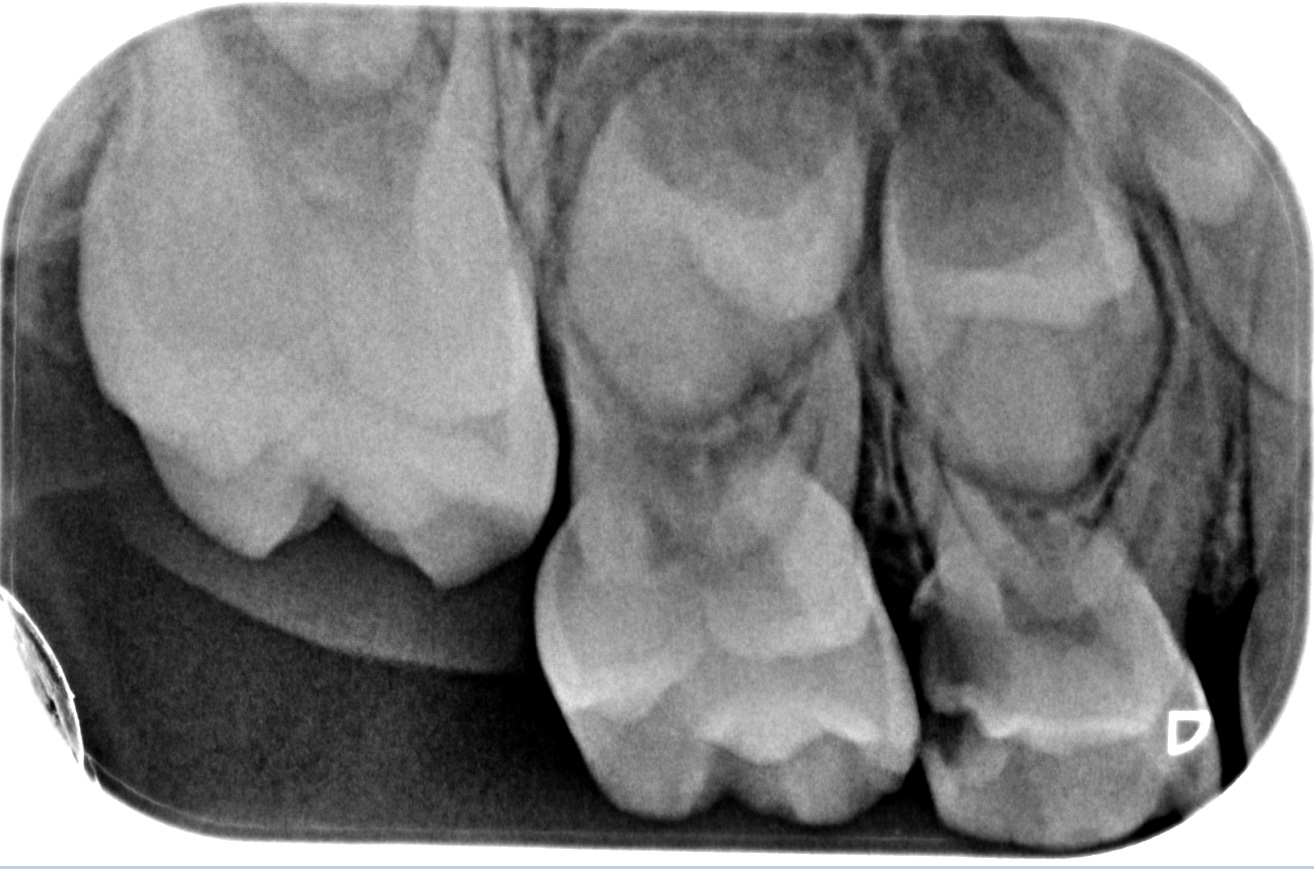

We use rotary nickel-titanium instruments, activated irrigation for deep disinfection, and modern bioceramic sealers for a dense, long-lasting seal. - Targeted diagnostics

- Clinical assessment and plan

We examine the tooth, test its response, and take focused images. When roots are complex or a previous treatment failed, a small 3D scan may be needed for mapping before we discuss and agree on the plan. - Anaesthesia and comfort